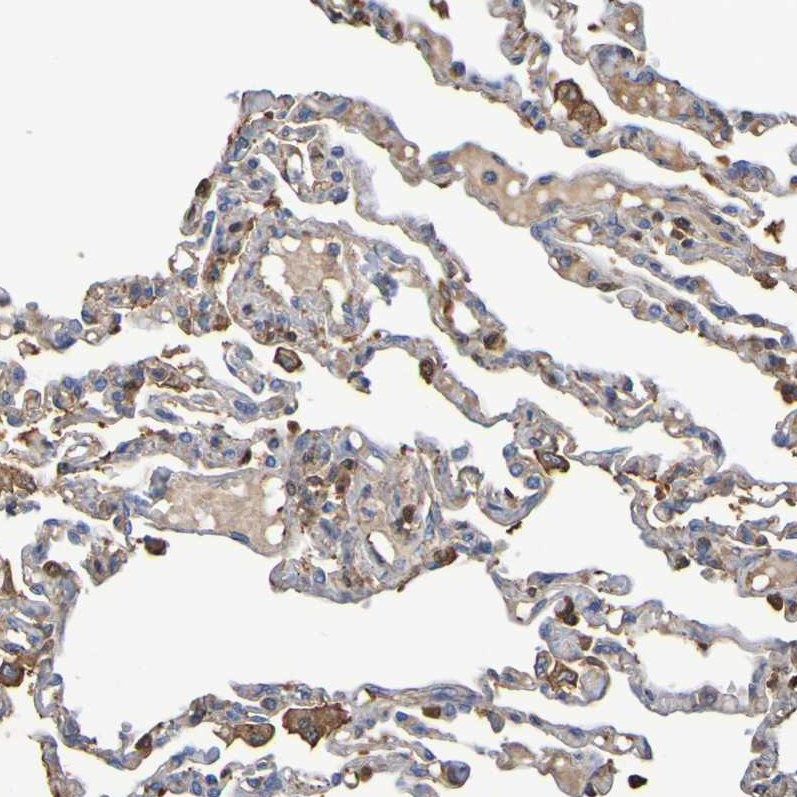

Immunohistochemical staining of human lung shows moderate membranous positivity in macrophages.